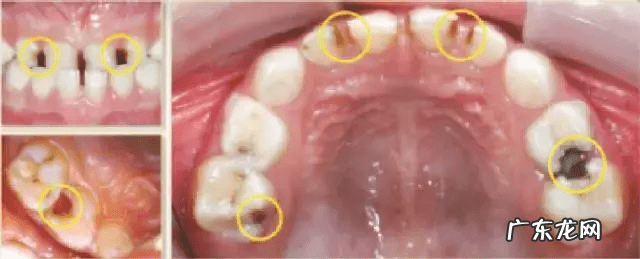

乳牙龋

乳牙龋的发生最常见的原因是口腔中的细菌,以日常食品中摄入的糖为食物,代谢产物为酸,酸会腐蚀牙釉质,最终形成龋齿 。

乳牙龋的特点

- 乳牙龋有两大特征:

①进展快,就是当家长发现黑色的时候,往往乳牙已经累及牙髓 。

②自觉症状不明显,即当龋病刚刚发生的时候多数儿童不会感觉明显疼痛,因为乳牙的神经发育不完善 。